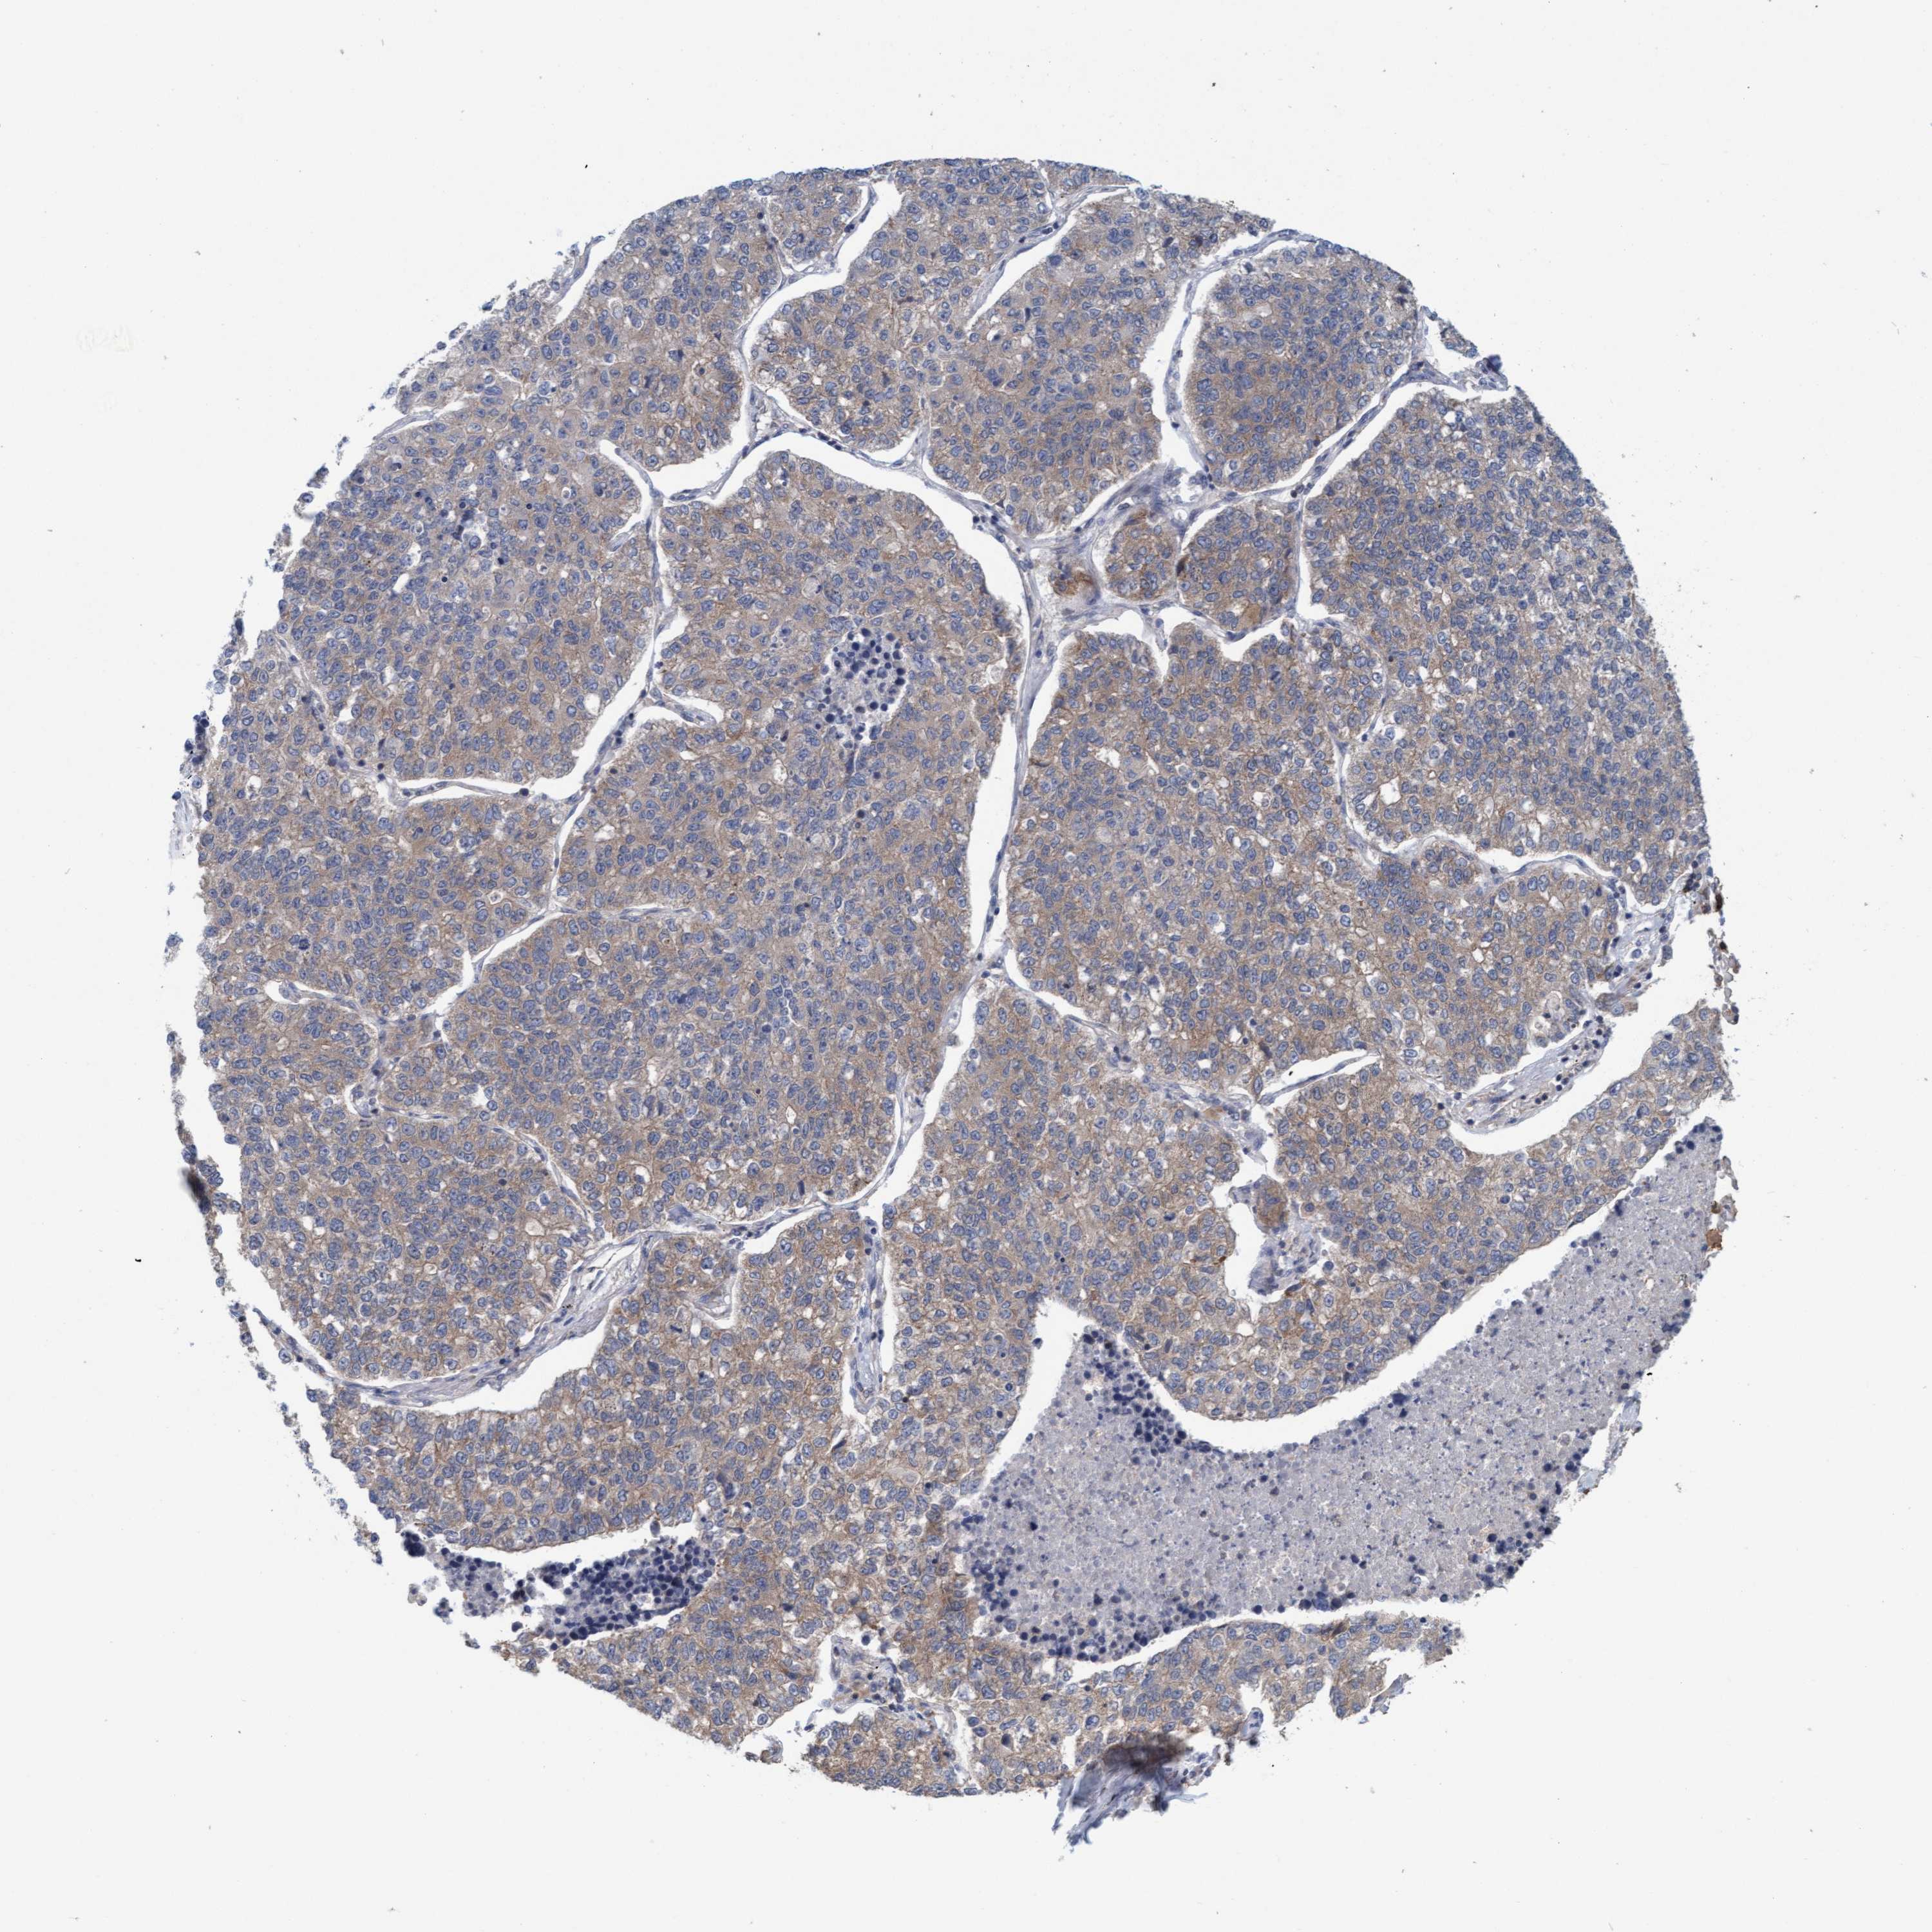

LUNG ADENOCARCINOMA (VALIDATION) - Interactive survival scatter ploti

The Survival Scatter plot shows the clinical status (i.e. dead or alive) for all individuals in the patient cohort, based on the same data that underlies the corresponding Kaplan-Meier plots. Patients that are alive at last time for follow-up are shown in blue and patients who have died during the study are shown in red.

The x-axis shows the expression levels (FPKM) of the investigated gene in the tumor tissue at the time of diagnosis. The y-axis shows the follow-up time after diagnosis (years). Both axes are complimented with kernel density curves demonstrating the data density over the axes. The top density plot shows the expression levels (FPKM) distribution among dead (red) and alive patients (blue). The right density plot shows the data density of the survived years of dead patients with high and low expression levels respectively, stratified using the cutoff indicated by the vertical dashed line through the Survival Scatter plot. This cutoff is automatically defined based on the FPKM cutoff that minimizes the p-score. The cutoff can be changed by dragging the vertical line or by entering a cutoff value in the square labeled "Current cut-off".

Under the Survival Scatter plot the p-score landscape (black curve; left axis) is shown together with dead median separation (red curve; right axis). Dead median separation is the difference in median mRNA expression between patients who have died with high and low expression, respectively. It is calculated as follows: median FPKM expression of dead patients with high expression - median FPKM expression of dead patients with low expression. This is intended to aid the user in visually exploring custom cutoffs and the associated p-scores and dead median separation.

Individual patient data is displayed and can be filtered by clicking on one or more of the category buttons on the top of the page. Categories describing expression level and patient information include: high, low, alive, dead, female, male and tumor stages. The scale of the x-axis can be toggled between linear and log-scale by clicking on the "x log" button. Mouse-over function shows TCGA ID, patient information and mRNA expression (FPKM) for each patient.

& Survival analysisi

Kaplan-Meier plots summarize results from analysis of correlation between mRNA expression level and patient survival. Patients were divided based on level of expression into one of the two groups "low" (under cut off) or "high" (over cut off). X-axis shows time for survival (years) and y-axis shows the probability of survival, where 1.0 corresponds to 100 percent.

FXR2 is not prognostic in Lung Adenocarcinoma (validation)

Best expression cut offi

: 25.47

P scorei

N/A

TCGA RNA samplesi

RNA-seq data is reported as average FPKM (number Fragments Per Kilobase of exon per Million reads), generated by the The Cancer Genome Atlas (TCGA) .

Normal distribution across the dataset is visualized with box plots, shown as median and 25th and 75th percentiles. Points are displayed as outliers if they are above or below 1.5 times the interquartile range. FPKM values of the individual samples are presented next to the box plot.

Average pTPM 20.6

Number of samples 105